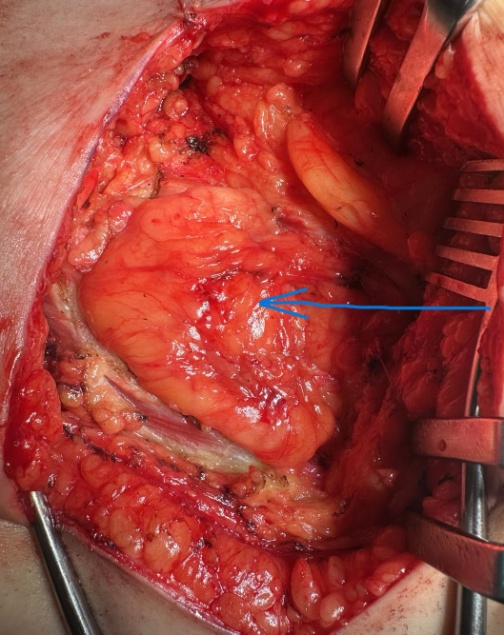

Πράσινο βέλος — Εγγύς νήστιδα. Μπλε βέλος — Απόστημα (Ευγενική παραχώρηση Dr. V. Penopoulos).

Πράσινο βέλος — Στόμαχος. Κόκκινο βέλος — Απόστημα (Ευγενική παραχώρηση Dr. V. Penopoulos).